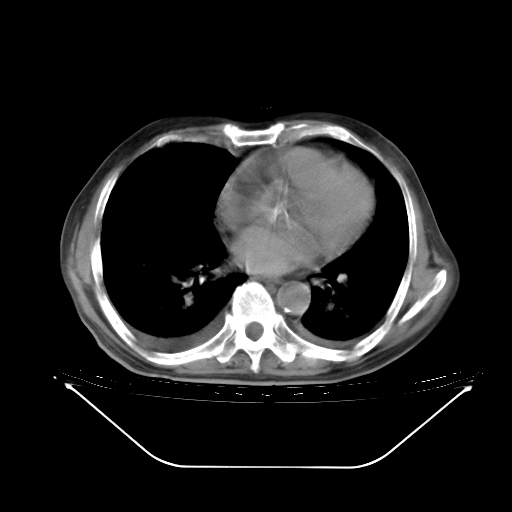

今天复查肺部CT,发现双肺广泛磨玻璃样改变。所以我把3月19日和5月9日相隔50天的肺部CT上传。请大家会诊。

2009年3月19日肺部CT片。

2009年3月19日肺部CT